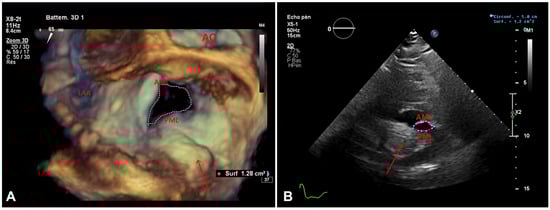

Figure 3.

A. Transoesophageal echocardiogram, three-dimensional planimetry of the mitral valve orifice (surgical view) and the (arrow). PML: posterior mitral leaflet; AML: anterior mitral leaflet, AO: aortic valve, LAA: left atrial appendage. B. Transthoracic echocardiogram, two-dimensional planimetry of the mitral valve orifice on parsternal short axis view and the c(arrow). PML: posterior mitral leaflet: AM anterior mitral leaflet.

Table 1). The patient was admitted for oxygen supplementation and intravenous diuretics with rapid recovery ensuing in a few days. A TTE documented normal heart function but an increase in the size of the cardiac mass ( 46 mm × 31 mm compared with 36 mm × 27 mm 4 years before), the mean gradient across the mitral valve was unchanged at 6–7 mm Hg at a heart rate of 65 bpm (

Figure 2) The mitral valve area obtained by two-dimensional planimetry from the parasternal short axis view was 1.2 cm

2 (

Figure 3B). No other significant valve disease was found. Transoesophageal echocardiography (TOE) showed moderate mitral stenosis. The mitral valve orifice measured by three-dimensional planimetry was 1.4 cm